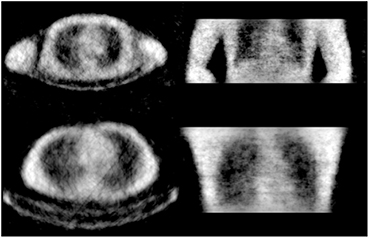

3.3. Reconstructions of cold human volunteers

A study of human subjects was performed in order to observe how well the method performs for the complex structure of the human body. The scan duration times were set to 10 min to simulate fairly realistic scan times and minimize movement from the volunteers. Each volunteer was placed on the bed and inserted into the PET field of view with no activity in or around the PET scanner. A corresponding blank was acquired for 36 h and used for reconstructions of the attenuation maps. The reconstruction algorithm parameters used were 10 iterations with 24 subsets with some regularization for all human volunteer studies. No corrections were performed to the data that corrects for object originating physical effects to the transmission gamma such as scatter or attenuation.

Figure 6 shows two volunteer scans of the head with a carbon fiber head holder in the field of view. From the figure the sinus are visible and the head holder and outline of the head are well defined. Some high density regions are also visible such as parts of the skull and teeth.

Figure 6. Reconstructed transmission image of volunteer's head with head holder. Acquisition performed for 10 min.

Download figure:

Standard image High-resolution imageFigure 7 are reconstructed images of the torso regions of males with weights of ~70 kg. The study of the torso region was performed with both arms up and arms down in a relaxed position. Arms are usually up in a clinical scan unless it is not practical. The arms down case can suffer from truncation of the CT. Using transmission data from Lu-176, the field of view for the attenuation maps are matched to the PET field of view. From both studies, body outline is resolved and internal details such as lungs and the heart are visible. The two studies also differ as the arms down case had the volunteer laying directly on the carbon fiber bed and the arms up case had the volunteer laying on a foam mat between the body and the bed. The bed is easily seen in both images but only having the whole bed visible when the volunteer is lying on a foam mat that separates the body from the bed. The patient's arms up while lying on the foam mat is the typical clinical procedure for imaging in the torso region.

Figure 7. Reconstructed transmission images of volunteer's torsos. Studies were performed with both cases of arms down (top) and arms up (bottom) with acquisition time of 10 min.

Download figure:

Standard image High-resolution imageFigure 8 shows a larger volunteer of weight of ~ 180 kg that would experience truncation within the CT FOV. This study was performed with arms down and 10 min. The circle illustrates the CT's 50 cm FOV and demonstrates even if this study was performed with arms extended overhead, truncation would still occur to this volunteer. It is observed that the body contour is still resolved and some internal structures are visible such as the lungs and heart, but not as clear as the smaller volunteers' case.

Figure 8. Reconstructed transmission image of large human volunteer. Circle illustrates the CT's FOV.

Download figure:

Standard image High-resolution image3.4. Reconstruction of emission data with Lu-176 attenuation maps